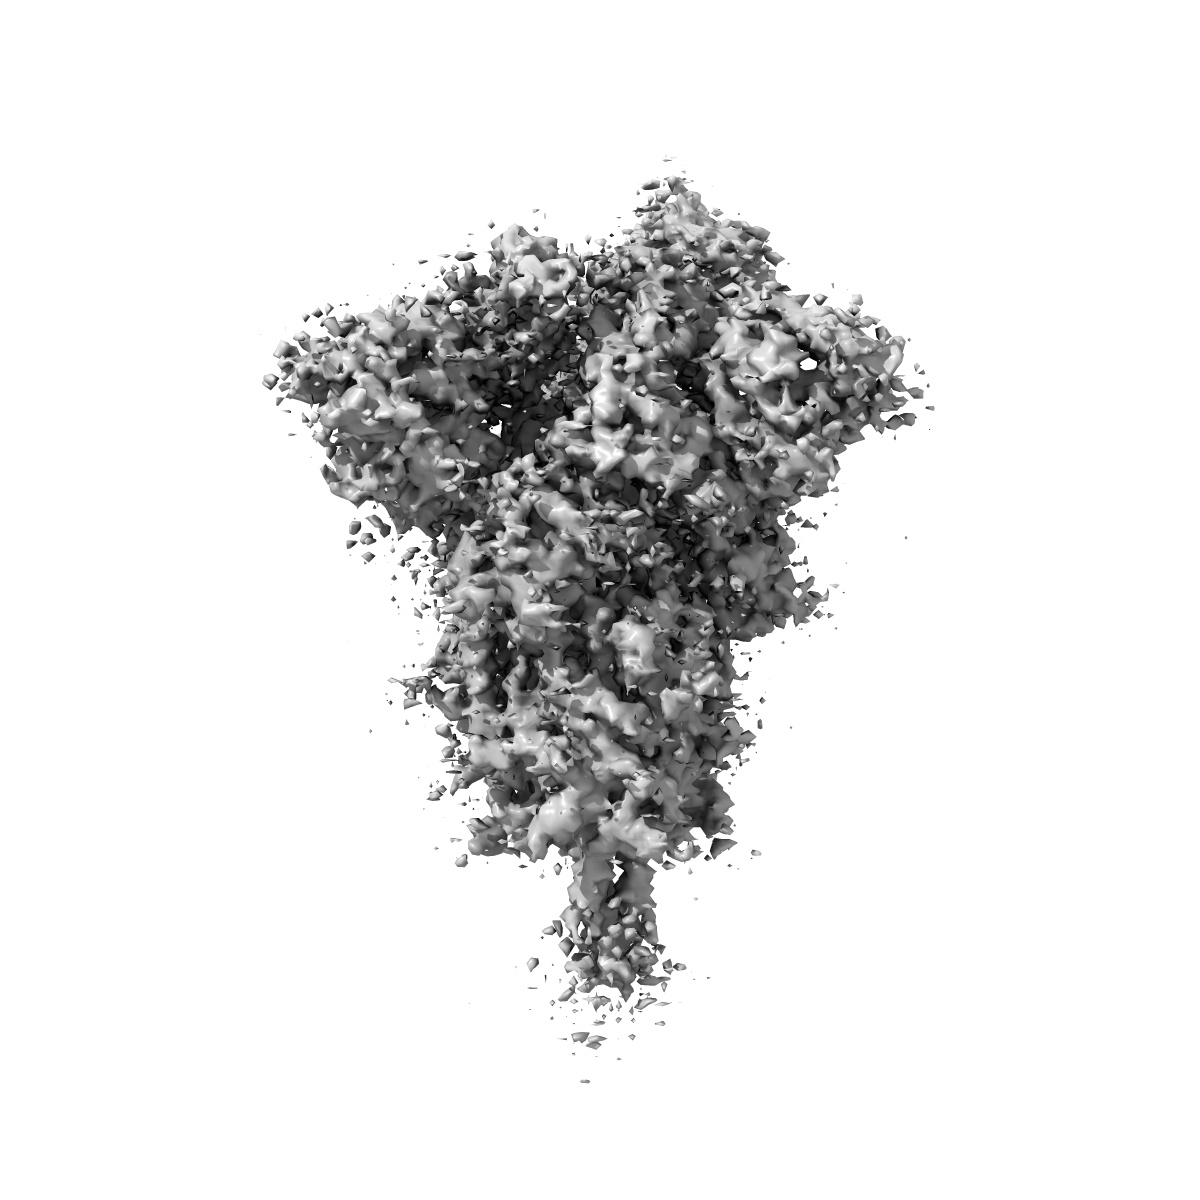

Spike_GSAS_6P and R1-32 Fab with 3to1 ratio

Single-particle4.75 Å

Sample: SARS-CoV-2 S-GSAS/6P spike trimer bound to R1-32 Fab with 3:1 ratio